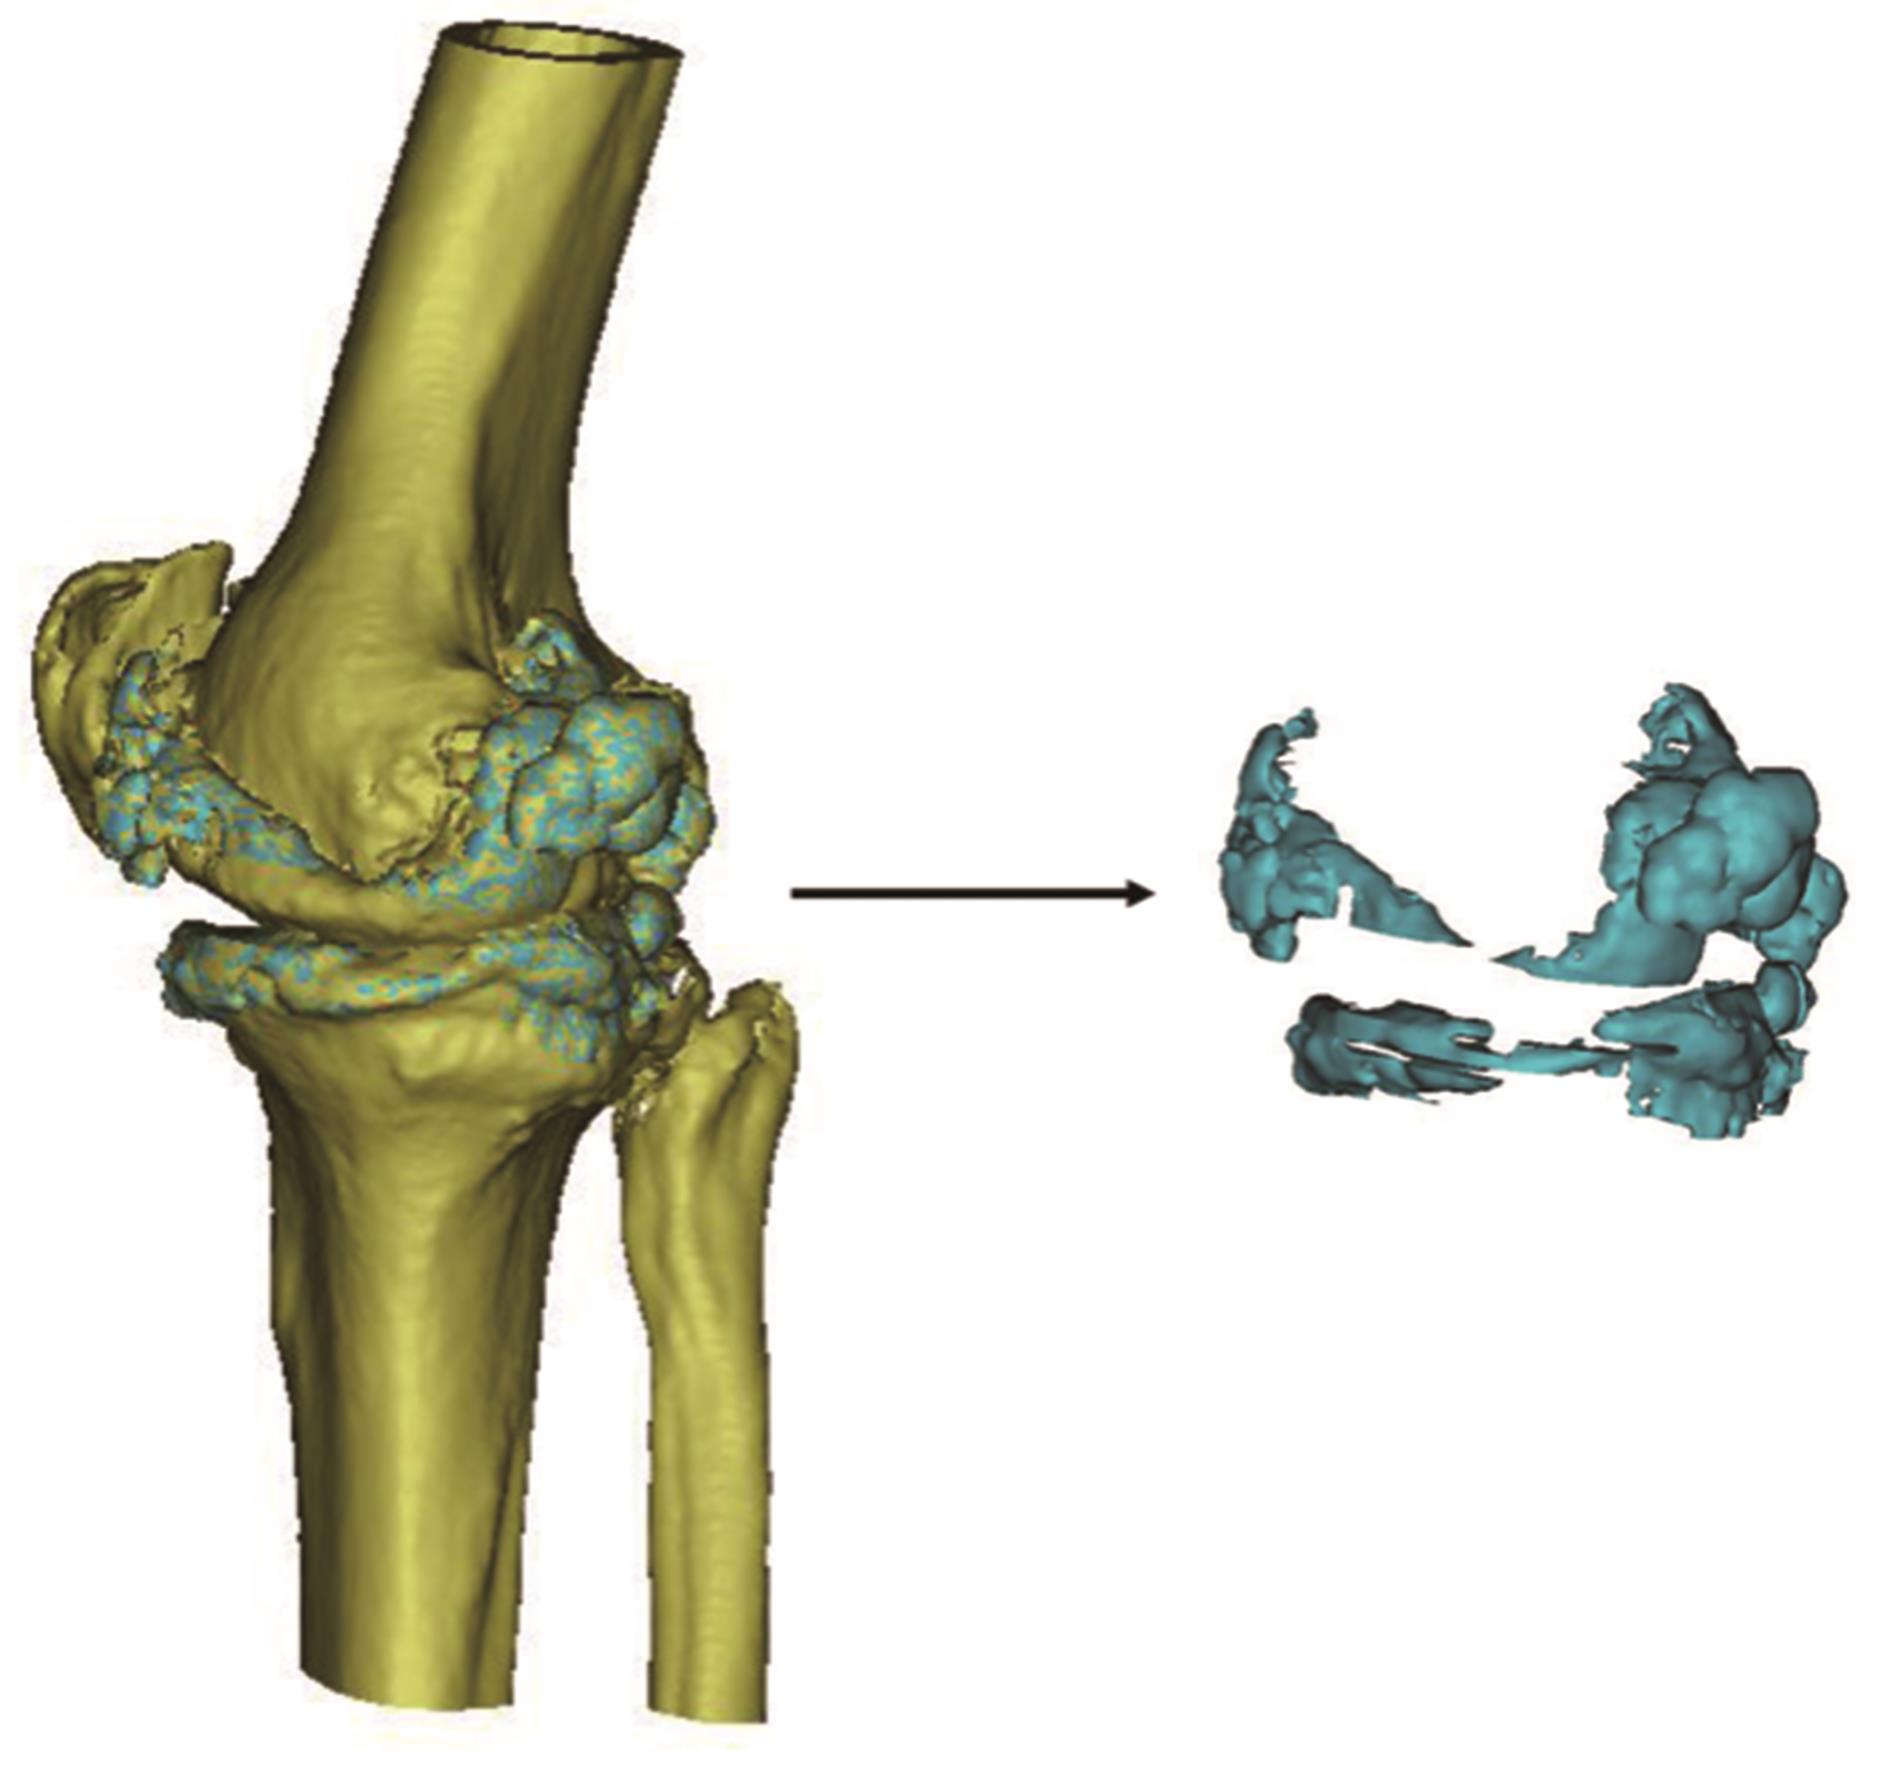

• 自体股骨头结构植骨重建髋臼辅助THA在改良CROWE Type ⅣB型DDH中的临床疗效分析

2024, 49(3):340-345. DOI: 10.13406/j.cnki.cyxb.

摘要 (37) HTML (42) PDF 4.06 M (60) 评论 (0) 收藏

摘要:目的 分析和总结自体股骨头结构植骨重建髋臼辅助全髋关节置换术(total hip arthroplasty,THA)治疗改良Crowe Type ⅣB型成人髋关节发育不良性脱位(developmental dysplasia of the hip,DDH)患者的临床疗效。方法 按照改良Crowe分型,选取山东大学齐鲁医院德州医院关节外科2015年8月至2023年3月收治的Type ⅣB型DDH患者26例,其中男25例,女1例,采用自体股骨头结构植骨重建髋臼辅助THA,记录患者手术时间、术中失血量、术中术后输血量、术后血红蛋白、手术相关并发症和骨愈合时间等,并行骨盆正位X线片了解假体位置、假体骨长入、假体松动以及骨愈合情况等,采用视觉模拟评分表(visual analogue scale,VAS)评价髋关节的疼痛不适,采用髋关节Harris评分和Western Ontario and McMaster Universities Osteoarthritis Index(WOMAC)来评价髋关节功能及临床疗效。结果 所有患者的平均随访时间(9.73±8.35)个月,术中出血平均为(715.38±143.37) mL,术中平均输血(415.38±282.41) mL,手术时间平均为(118.62±18.27) min,术后平均输血为(192.31±236.51) mL。所有患者转子下骨端、自体股骨头和假臼之间均骨愈合良好。髋关节VAS评分从术前6.73±0.45,至术后末次随访时VAS评分1.73±0.53,差异有统计学意义(P=0.000),髋关节活动度均较术前明显改善,髋关节Harris评分从术前24.27±1.66,至术后末次随访时Harris评分74.77±2.89,差异有统计学意义(P=0.000),WOMAC术前术后评分分别为130.08±5.72和67.85±3.23,差异均有统计学意义(P=0.000)。结论 自体股骨头结构植骨重建髋臼辅助THA治疗改良Crowe Type ⅣB型DDH,具有操作相对简单、固定牢固、手术相对安全和疗效确切的优点。